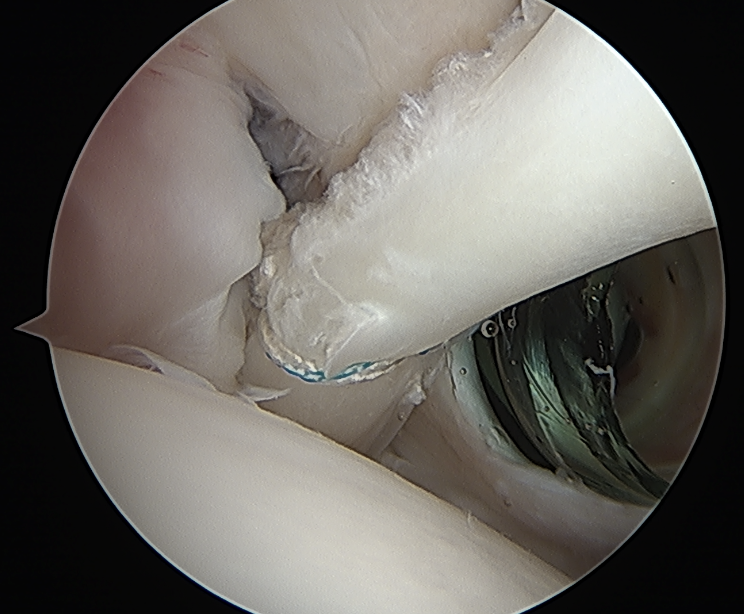

Tendonopathy

Medial subluxation of LHB